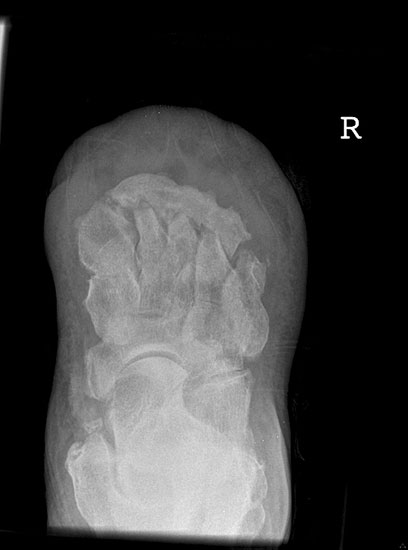

Kalkaneusteilamputationen, Kalkaneusresektion

Indikationen

• Weichteildefekte, die weder konservativ noch plastisch-chirurgisch zu decken sind,

• Lokale Osteomyelitiden mit Knochennekrose und Weichteilbeteiligung (Abb. 50).

• Kontraindikationen

• Bei einer fortgeschrittener PAVK ist eine Calcaneus-Resektion selten ausreichend. Falls nicht eine höhere Amputation indiziert ist, ist meist eine Revaskularisation zusätzlich erforderlich (Abb. 51).

Das Ausmaß der Knochenresektion ergibt sich aus der Defektgröße bzw. aus der Ausdehnung der Osteomyelitis 3 (Abb. 52). Eine totale Kalkanektomie ist problematisch, weil danach die Leitungsbahnen unmittelbar dem Körpergewicht ausgesetzt sind.